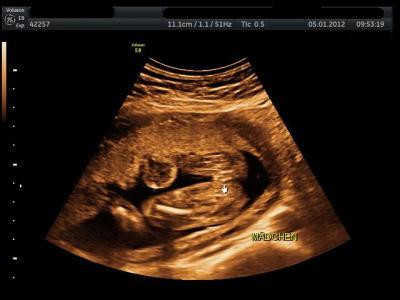

Hier mal ein Outingbild von meinem Mädchen :)

wenn ihr mal gucken wollt Sonst wird die Musch nie wieder gezeigt

Eindeutig,würde ich mal sagen!!!

Ja, das sieht wohl ganz klar nach einem Mädchen aus LG Diana

Wow, da sieht man es ja richtig :-) Tolles Bild Bei meiner Kleinen konnte man es auch so gut sehen, wir haben aber leider kein Bild bekommen. LG